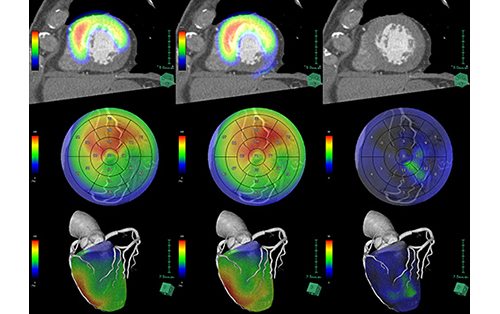

心臓フュージョンでは、機能画像と形態画像を重ね合わせて、互いの特長を生かした画像を生成できます。CTだけでなく、MRIで得られた心機能の情報、遅延造影解析の結果、またはSPECT画像とのフュージョンも可能です。

心臓CT・MRIパフュージョンの検査データから心筋の虚血状態を解析できます。

CT・MRIで撮影された遅延造影画像から信号値が高い領域を抽出し、面積を計算して高信号領域のブルズアイ表示、体積測定などを行います。遅延造影解析(CT)ではECV解析にも対応しています。